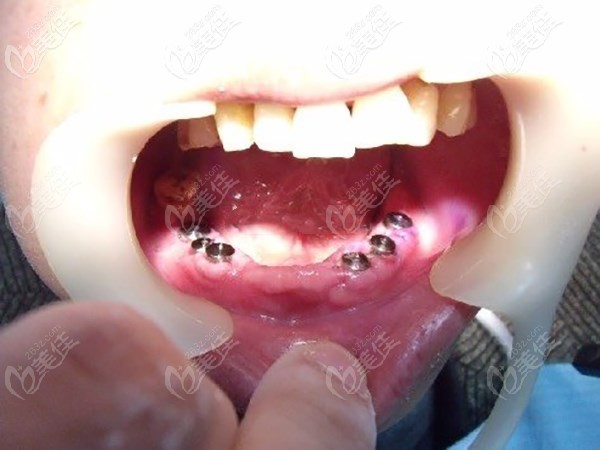

牙齿症状:70岁的李大爷,上牙松动,下牙坏死并缺失多颗,残存的牙齿大多也松动了。

种植体:德国icx ALL-ON-6种植修复。

从上图可以看出老人下牙坏死并缺失多颗,残存的也都松动了,根据老人牙槽骨条件,医生给老人的建议是做半口种植牙修复,这个技术院内做的比较成熟,成功率也比较高,老人可能对这个也不了解,说是要考虑考虑。

在麻药的作用下,很快就种好牙齿,医生说术后根据个人体质不同,有的人没感觉,有的人只会有轻微肿胀不适,不会有很大的疼痛,老人说他自己没啥感觉。